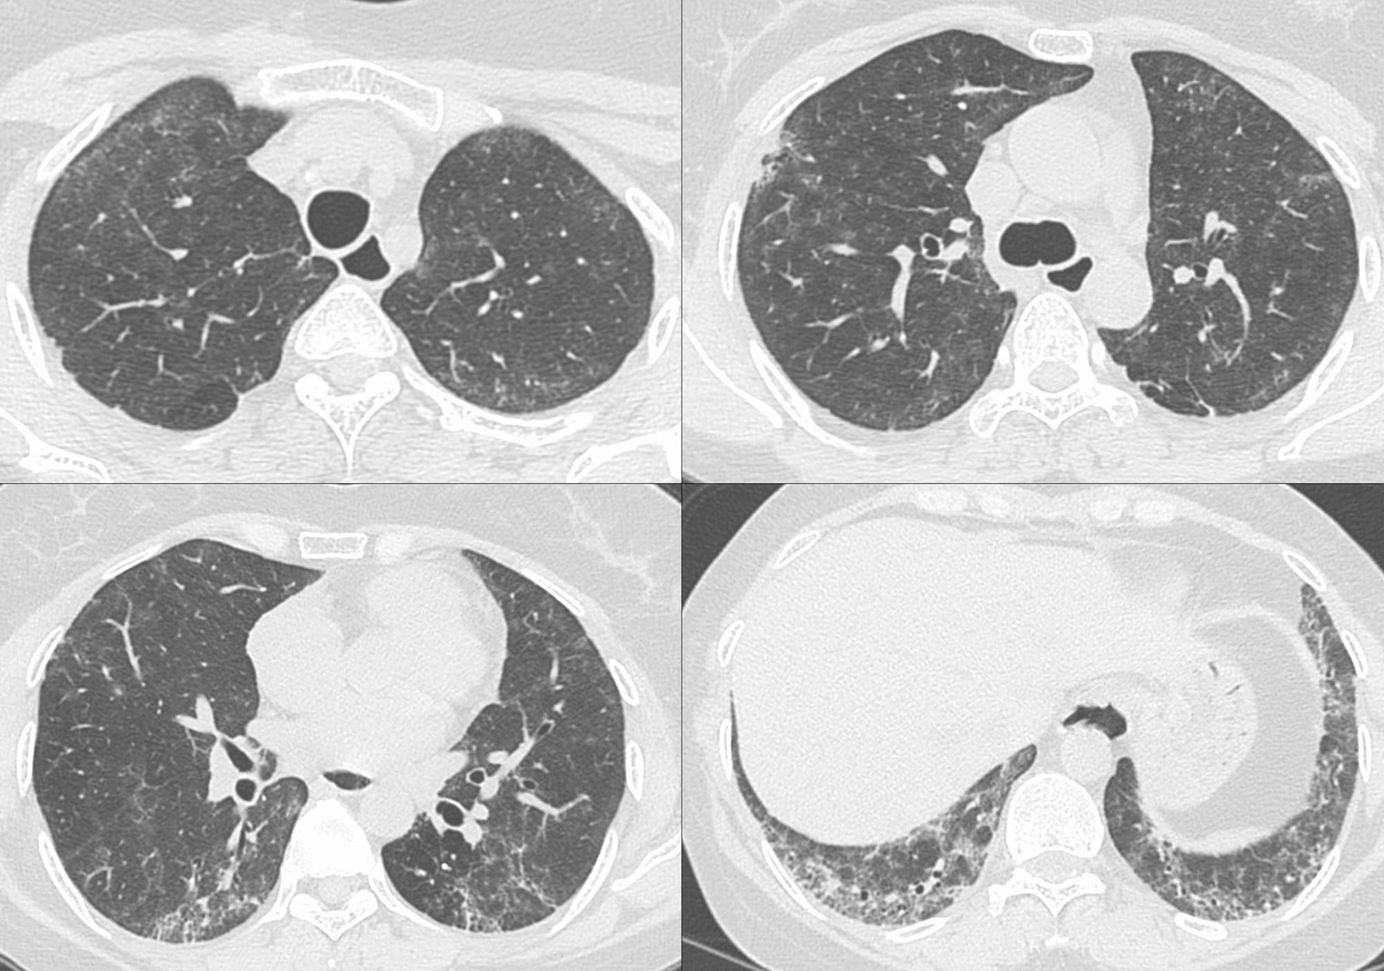

70-years old diagnosed to have ILD on an Aug 2025 CT scan.

A repeat CT scan showed interstitial lesions. The question is are they "real" and imply interstitial lung abnormality disease (ILD) or they are mimics.